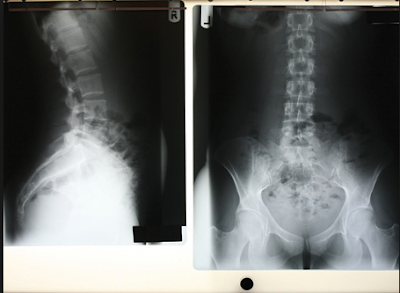

Raio-X da coluna vertebral

Espinhal raios-X são imagens da coluna vertebral. Eles podem ser tomadas para encontrar lesões ou doenças que afetam os discos ou articulações em sua coluna. Esses problemas podem incluir fraturas de coluna vertebral, infecções, luxações, tumores, esporões ósseos, ou doença do disco.

Espinhal raios-X também são feitos para verificar a curva da sua coluna (escoliose) ou por defeitos na coluna vertebral.

Tecidos densos do corpo, como ossos, bloco (absorver) muitos dos raios-X e olhar branco em uma imagem de raios-X. Tecidos menos densos, como músculos e órgãos, menos de bloquear os raios-X (mais dos raios-X de passagem) e parecido com tons de cinza em um raio-X. Raios-X que passam apenas através do ar olhar negro na fotografia.

A coluna é dividida em quatro partes. Portanto, há quatro tipos comuns de raios-X da coluna vertebral:

Coluna lombossacra de raios-X. Este teste de raios-X tira fotografias dos 5 ossos da parte inferior das costas (vértebras lombares) e uma vista dos cinco ossos fundidos na parte inferior da coluna (sacro).